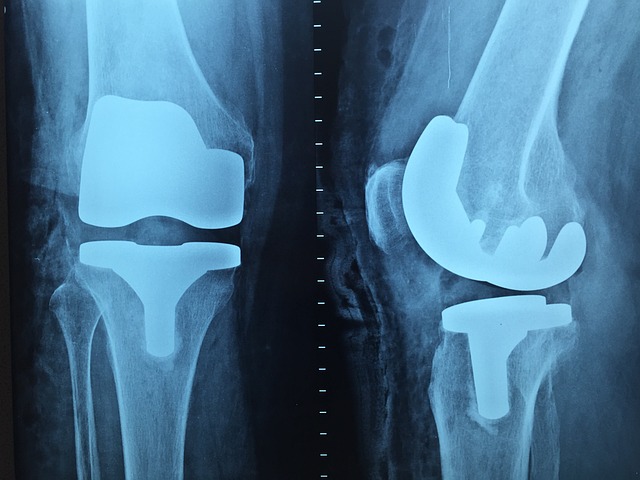

3. 영상 검사

X선, MRI, 초음파 등을 통해 관절의 상태를 확인합니다.

관절의 손상 정도와 염증의 범위를 평가합니다.